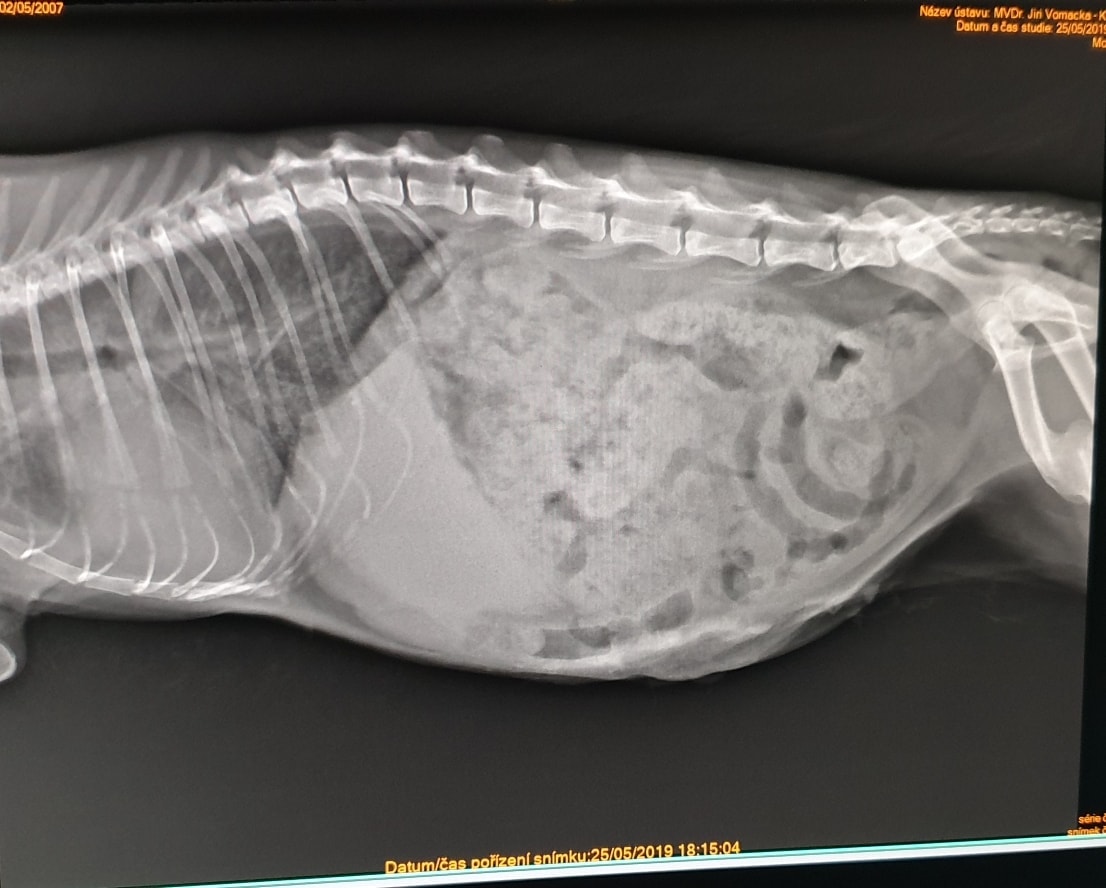

🔸Tam na nás již čekali. Pohotovostní službu měla paní doktorka ošetřující i Wariora. Nejprve několik RTG, sono a krev. Neznámá tekutina v břišní dutině, potíže s dýcháním, nic zlomeného. Obrovské srdce, vnitřní orgány zastřené. Zvláštní útvar v dutině břišní. Kočička byla dána na kyslík. A čekali jsme na stabilizaci. Podařilo se provést punkci a odebrat vzorek tekutiny. Pozdě večer se stav stabilizoval a dohodli jsme se na operaci – otevření. Operace byla dlouhá a zkončila pozdě v noci.